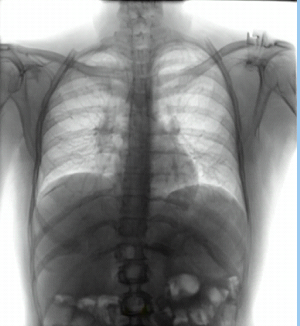

4.1 Qualitative Evaluation of Healthy Counterpart Generation

Example images from the disease COVID-19 Radiography Database and their generative healthy counterparts are given in figure 2. The images on the far left are instances of the lung opacity class from the real images in the dataset. The images in the middle column are examples of the generated healthy counterfactuals obtained via latent space diffusion, with RadBERT-guided textual-conditioning via a conditional prompt “normal chest x-ray”. A total of 75 diffusion inference steps are used with image conditioning strength=0.85 and guidance scale=7.5. (The former indicates the level of constraint on changes to the original input image and the latter is the weight given to the textual encoder conditioning in the generation of the image, ranging over [0,1] and [0,9], respectively).

Side-by-side inspection of the generated healthy counterfactuals (as per fig. 2) suggests that, as required, only minimal perturbation is made to the original image with respect to healthy pixels -i.e. localized image sites without structural medical defects. (In the top row, the medical structural defect in the original image is due to a lung opacity, and characterized via a relatively complex interaction between the imaging modality and subject manifesting as ‘gaps’ in the corresponding portions of the lung scan). The healthy/non-healthy discrepancy maps in all of these cases are obtained via masked subtraction of the original image from the generated image (the ground truth segmentation masks correspond to the broad area of interest –i.e. the complete lung). The generated healthy tissue is thus a subset of the mask and is shown in the final column of fig. 2 for the respective cases.

In the context of a VANT-GAN[20]-based approach, this highlighted material constitutes the diagnostic counterfactual visual attribution, i.e. the selection of material relevant to the diagnosis of the unhealthy condition. Healthy counterfactual generation was performed for the complete datasets in the three unhealthy classes, i.e Lung opacity, Viral Pneumonia and COVID, examples of which are given in fig. 3 for the three classes (all of the generated healthy counterfactuals from this experiment can be found on https://huggingface.co/ammaradeel/diffusionVA). Visual inspection indicates that the generated counterfactuals are, in general, visually plausible with minimal perturbation made to the unhealthy image overall. Moreover, the healthy counterpart generation does not appear to unnecessarily affect aspects of the images unrelated to the medical condition, the model selectively making changes to the unhealthy regions in a structurally plausible manner, e.g. generating missing portions of the lung without generating extraneous lung material where it would be expected to normally exist (e.g. in the abdominal cavity).